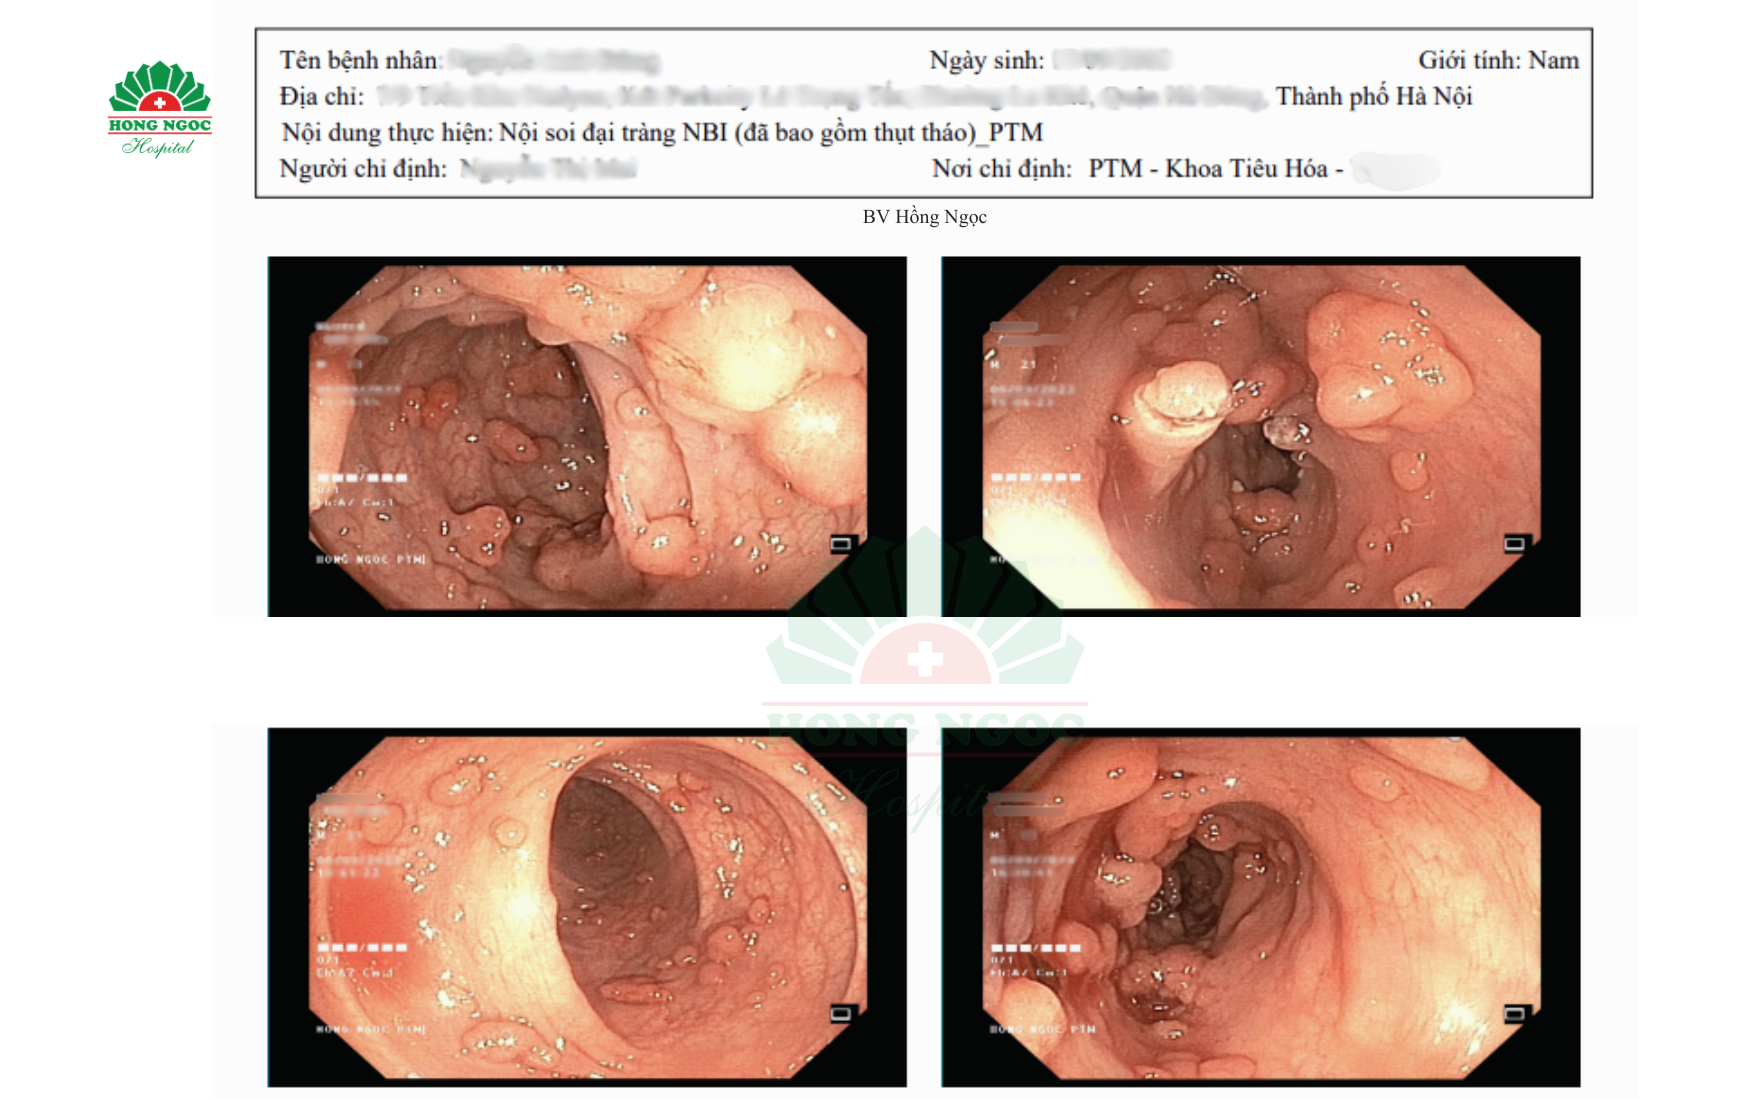

Hình ảnh nội soi cho thấy dọc đại tràng của bệnh nhân H có hàng trăm polyp mọc dày đặc, kích thước đa dạng từ 2-3mm đến 1,5 - 2 cm. Càng đi sâu vào lòng đại tràng, số lượng polyp càng tăng, kích thước lớn, một số đã có dấu hiệu biến đổi cấu trúc bề mặt, tiềm ẩn nguy cơ ác tính hóa thành ung thư. Bệnh nhân H được chẩn đoán mắc đa polyp tuyến gia đình.

Hình ảnh nội soi đại tràng phát hiện hàng trăm polyp của bn L.A.H